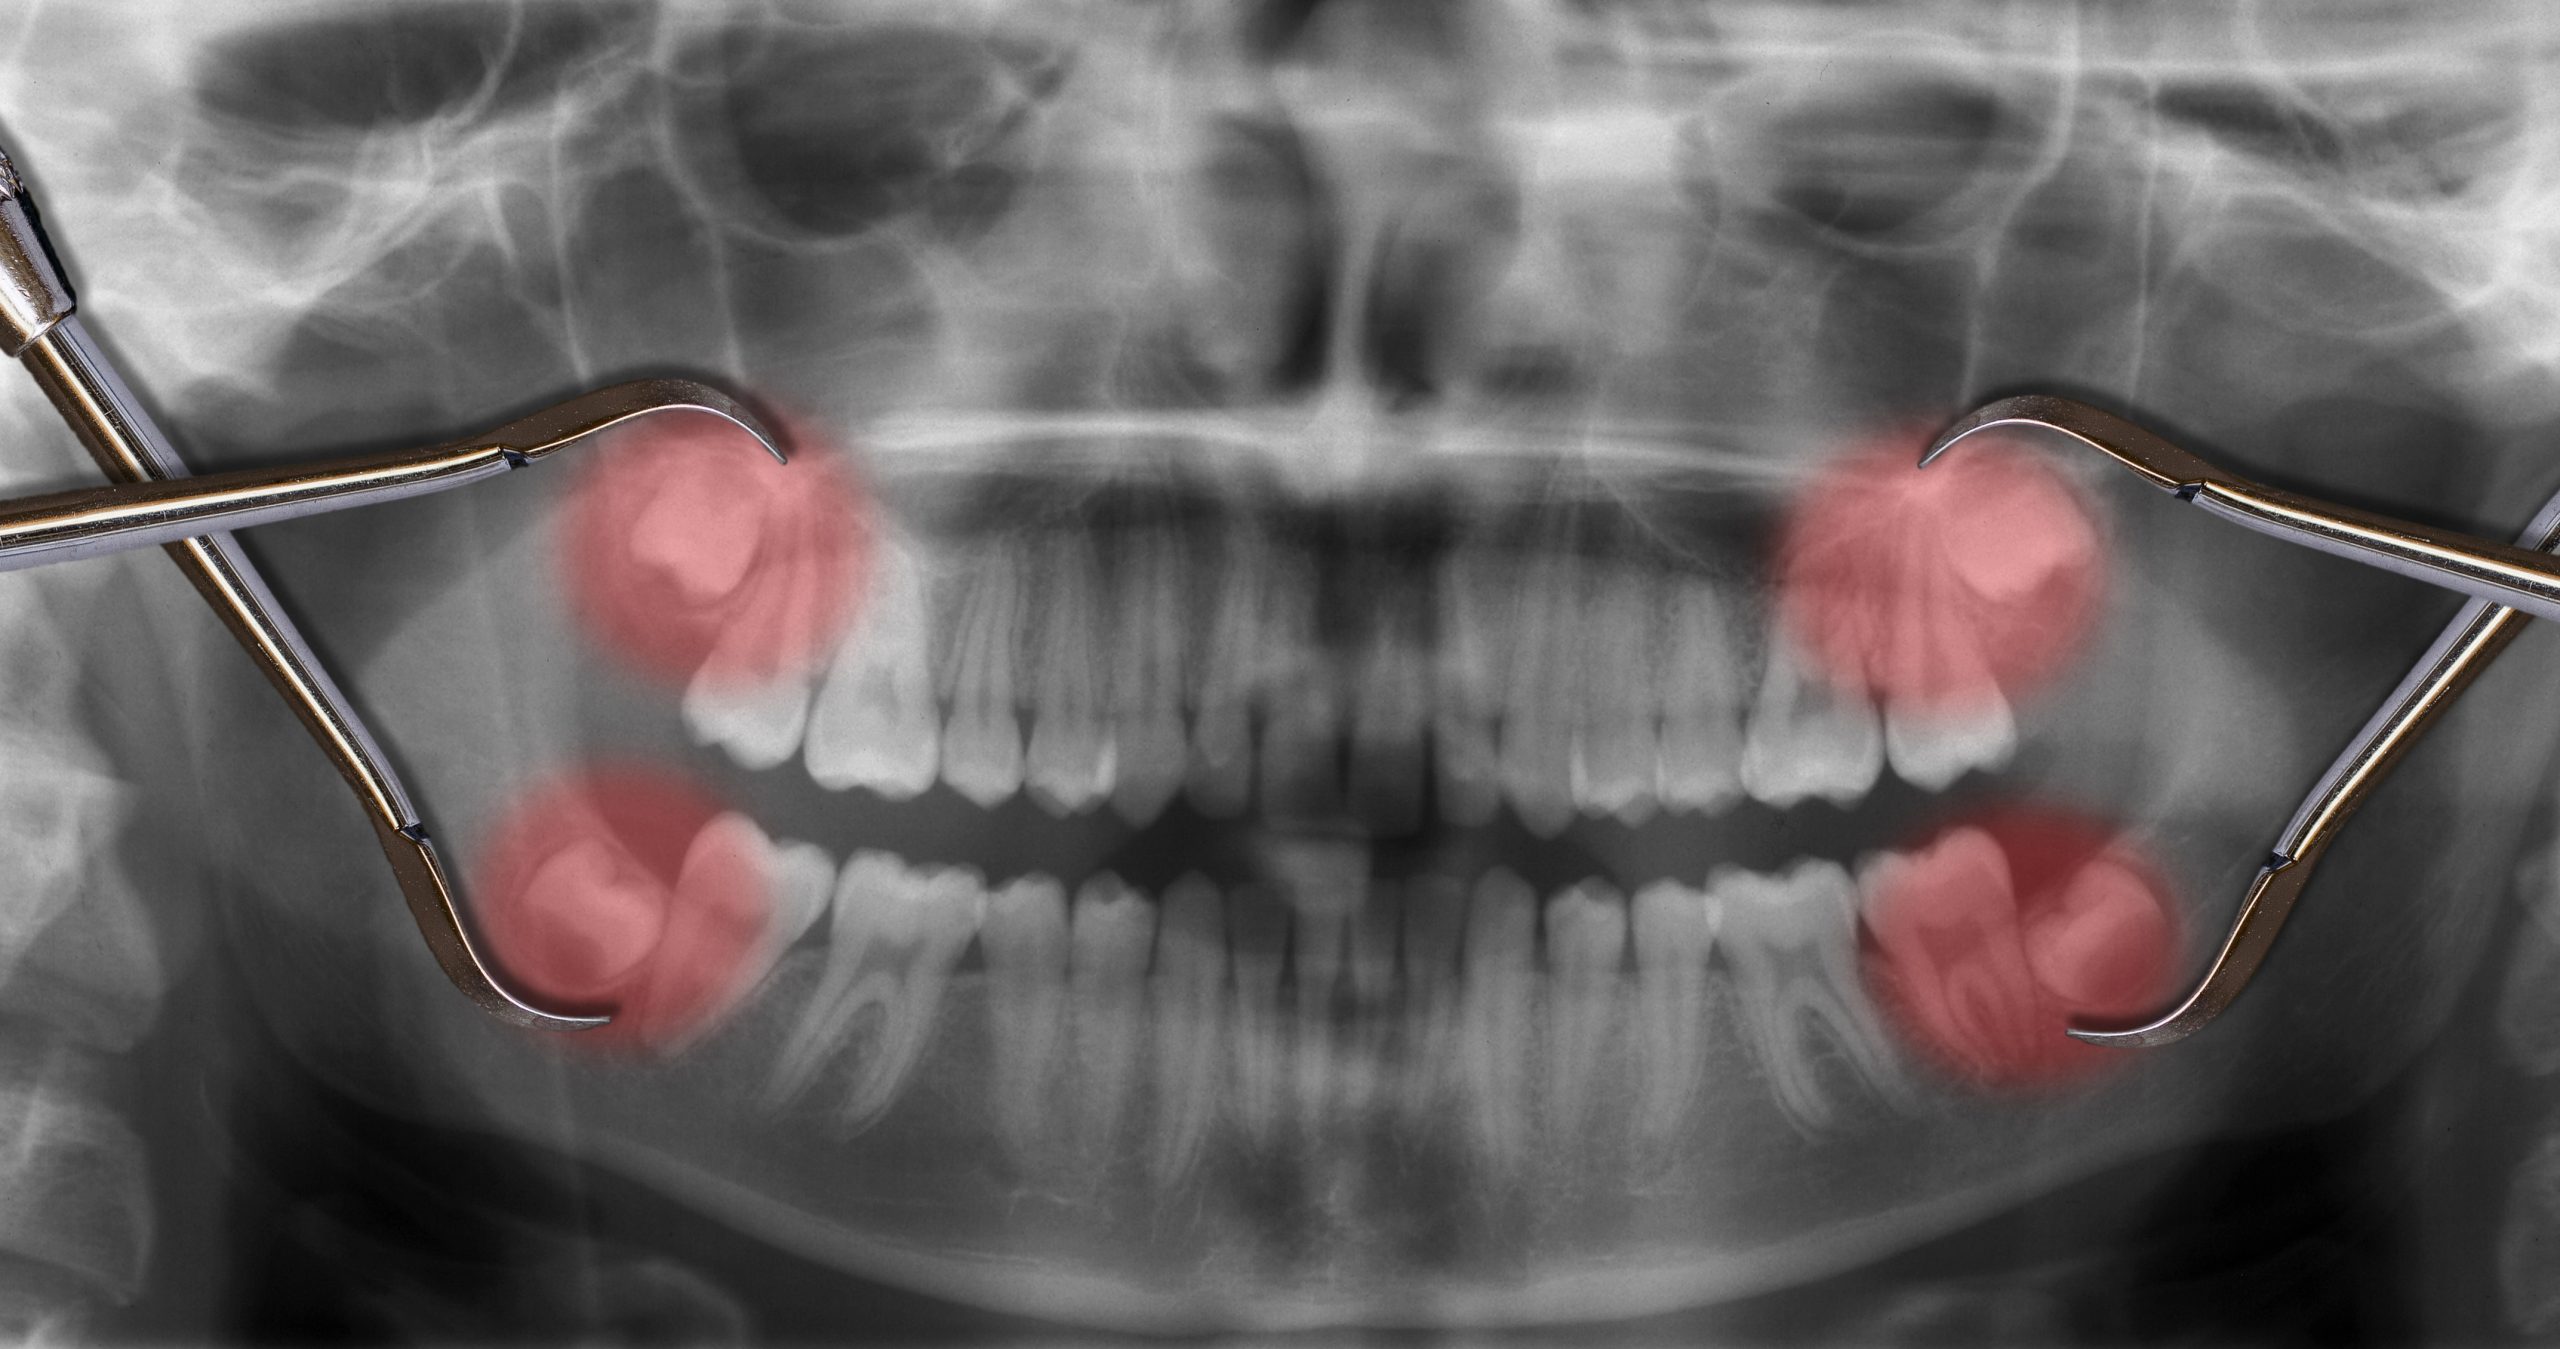

Dr is friendly and knowledgeable. Clinic is equipped with latest technology equipments. Takes necessary precautions while taking x-rays, eg. Covering patient with a shield.